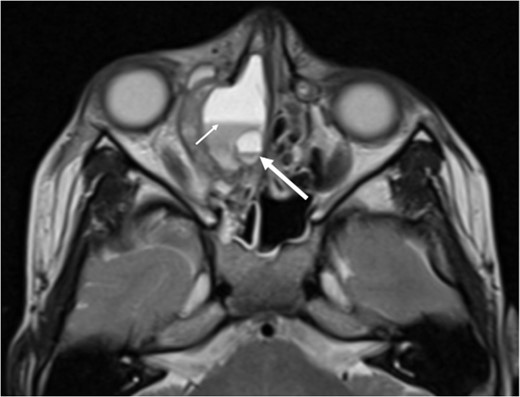

Axial T2 weighted sequence demonstrating the presence of multiple fluid filled levels (short white arrow) within the expansile lesion and smaller cyst present within the larger cyst (long white arrow).